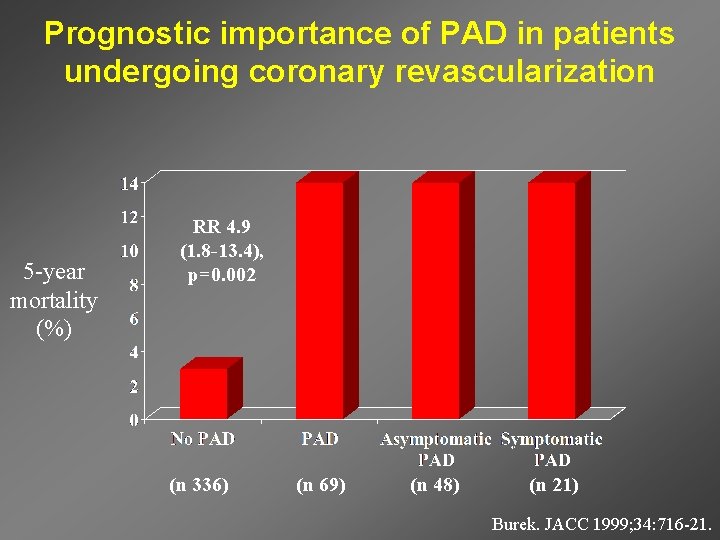

Prognostic importance of PAD in patients undergoing coronary revascularization 5 -year mortality (%) RR 4. 9 (1. 8 -13. 4), p=0. 002 (n 336) (n 69) (n 48) (n 21) Burek. JACC 1999; 34: 716 -21.